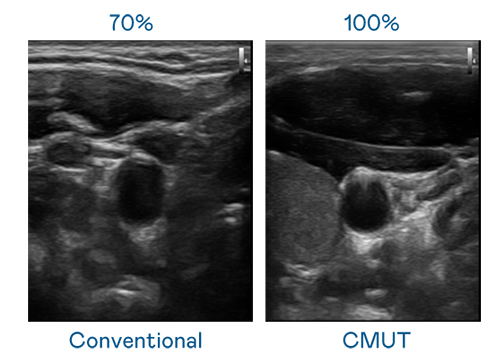

CMUT 技术是一种用电容式微机电元件来产生超音波讯号的技术。与传统 PZT 压电式技术相比,CMUT 频宽增加 30%,更宽频的超音波讯号让影像解析度大幅提升,是实现高影像品质医疗超音波扫描、促进精准医疗发展的关键技术。

大频宽带来超清晰影像

超音波影像的解析度高低,首先取决于探头能发出的讯号频宽。PA官方网站 CMUT 可提供高清晰的超音波讯号,提供高频宽、高灵敏度、影像纹理细节更高的超音波影像,协助医护人员缩短影像判读时间及利用精准的医疗影像进行诊断。